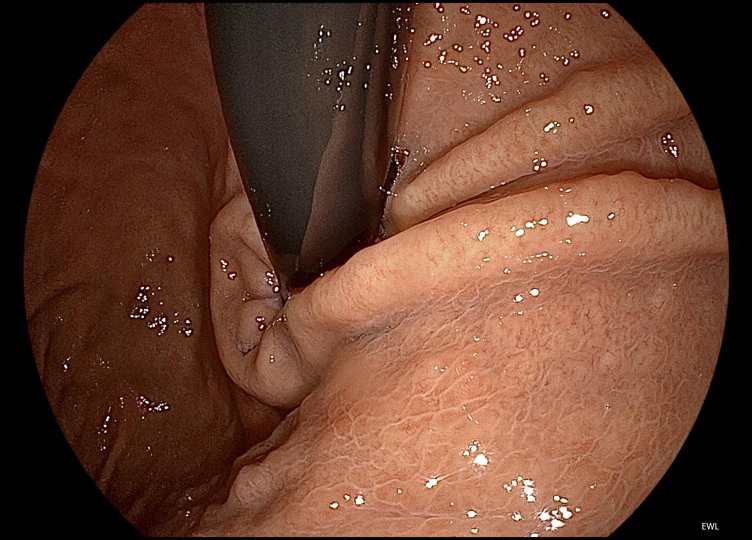

自适应融合调光(HAD):以往,面对胃腔等大腔体内镜观察,往往难以同时兼顾观察区域内近景和远景图像亮度。

而iEndo平台的HAD技术,可实时感知照明深度并匹配最佳调光策略及图像亮度处理算法,确保腔内近、远景亮度及清晰度始终保持在最佳状态,确保不因观察场景照明条件变化遗漏微小病变,为医生提供更精确的诊断支持。

▲HAD技术兼顾近、远景亮度和清晰度